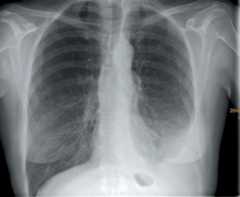

Imaging techniques

If a pleural effusion is suspected, a chest x-ray should be obtained (Figure 1) (9). A postero-anterior view reveals effusions of volume 200 mL or larger, a lateral view effusions of volume 50 mL or larger. A lateral decubitus view can be used to confirm the free flow of the effusion around the lung.

Figure 1:

Chest x-ray of a 59-year-old woman with a left-sided pleural effusion. Further work-up revealed a pleural mesothelioma as the cause.

Radiology Dept., Klinikum Würzburg Mitte, with the kind permission of Prof. H.-J. Langen